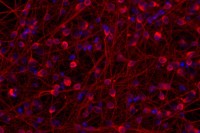

Seeing the Light: How Engineered Nerve Cells Might Curb Parkinson’s Disease

A new tool called optogenetics is revealing clues about the function of a promising experimental therapy derived from stem cells.

Researchers Fast-Forward Stem Cell Aging to Study Degenerative Diseases

A team of Memorial Sloan Kettering scientists has come up with an approach to make stem-cell-derived neurons rapidly age in a cell culture dish. The breakthrough could transform research into Parkinson’s and other late-onset diseases.